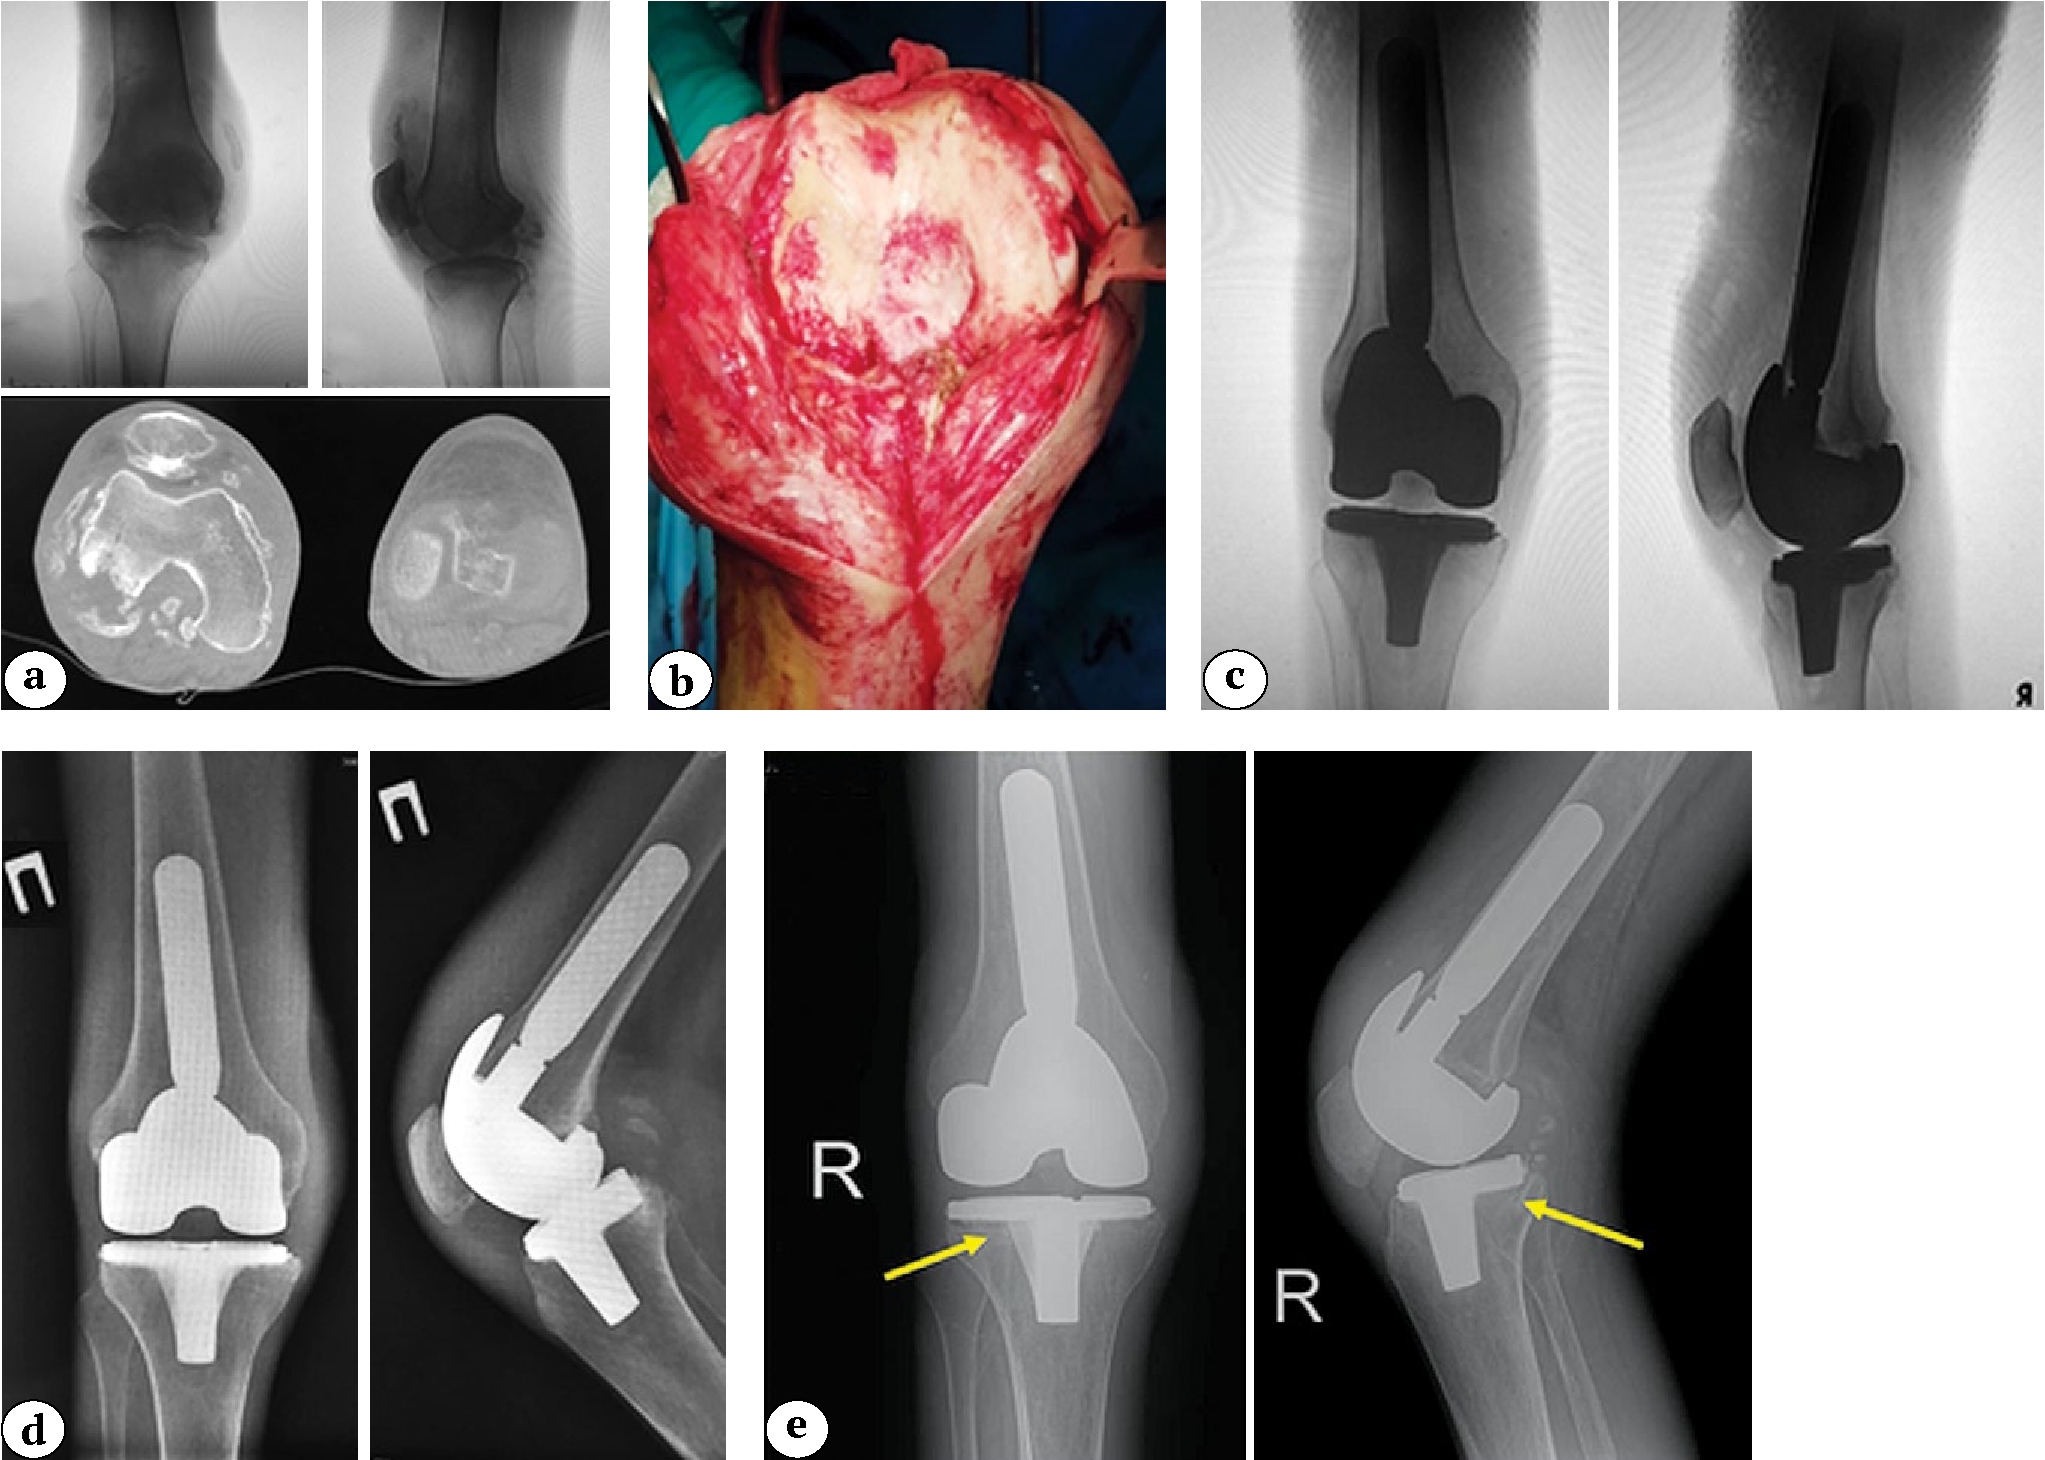

An example of a clinical case of aseptic loosening of the tibial component leading to infectious complications in a patient from Group 1 after primary knee arthroplasty is shown in Figure 3.

Fig. 3 (a, b, c, d, e). A 32-year-old man with secondary osteoarthritis of the right knee. Concomitant diseases: end-stage chronic kidney disease (5D stage), chronic hemodialysis for 7 years, type 1 diabetes: a — X-rays in two projections and CT scans before surgery: a bone defect is detected in the posterolateral part of the lateral femoral condyle b — knee after arthrotomy; c — X-rays after knee replacement (a revision femoral component and a standard 100 mm stem; the bone defect was replaced with two metal blocks of 5 mm and 10 mm, posterior-stabilized insert; standard tibial component); d — X-rays one year after knee replacement: no signs of osteolysis or component instability are observed; e — X-rays of the right knee three years after arthroplasty: radiolucent lines are noted in zones 3, 4, and 2 of the tibial component according to the KRESS (indicated by arrows)